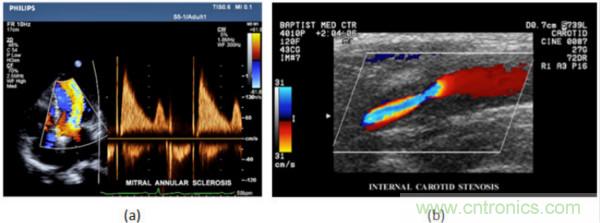

在CW和PW多普勒模式中,流信息是從一個聚焦聲束中獲得的,類似于A模式成像。在20世紀80年代,研究人員基于彩色多普勒技術完成了血流分布的二維信息可視化。彩色多普勒處理也是基于B模式/PW模式信號路徑。從感興趣區域收集多幀RF數據。由于感興趣區域中的血液流動導致圖像幀之間存在數據差異。相域中的自相關和時域中的互相關兩種算法可從RF數據中提取數據方差(即血流速度和方向信息):。根據預定義的顏色漸變條相應地映射包括速度和方向的血流信息。通常,藍色和紅色代碼分別識別朝向和遠離換能器移動的血流。當流速增加時使用更亮的顏色,反之亦然。顏色映射的2D分布始終疊加在B模式圖像上,以實時同時顯示個體解剖結構和血流。它對于診斷心血管疾病,如血管閉塞和心臟瓣膜反流,極其有用。典型的彩色多普勒圖像如下圖所示,(b)顯示頸動脈狹窄引起的血流流速變化。

圖7.彩色多普勒成像:(a)以彩色多普勒和CW模式獲得的圖像(由Philips提供); (b)顯示頸動脈狹窄的彩色多普勒(由GE提供)